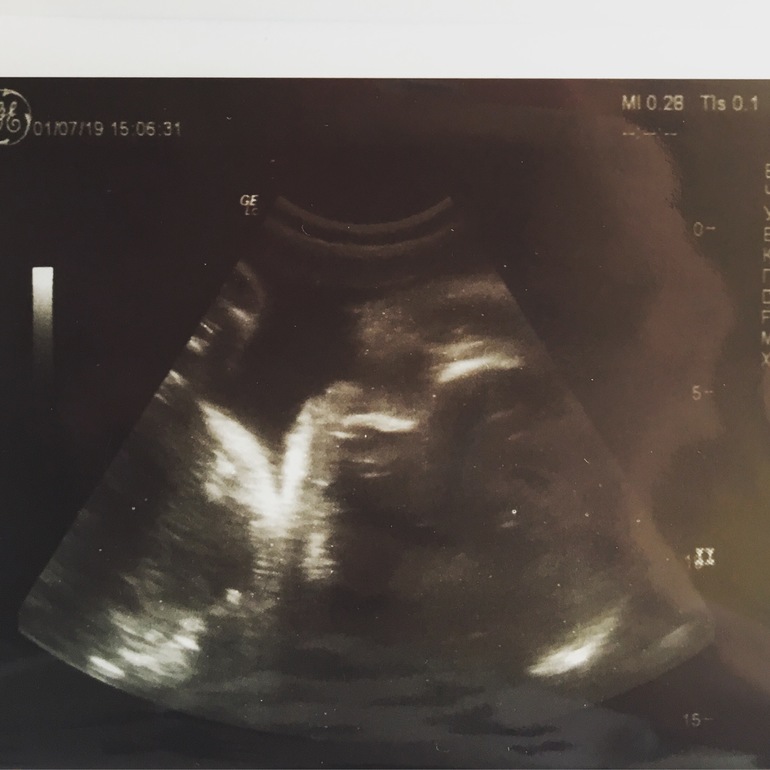

В прошлый понедельник (на сроке 35,2 нед) ходила на узи . Чисто спонтанно вышло - пошла с сыном к платному окулисту и решила записаться на узи, а тут окошко у врача свободное - пошла с сыном)) он смирненько сидел рядом со мной и наблюдал за братиком на мониторе.

По узи у нас все отлично! Сынок опережает срок на недельку, а вот ножки у него прям модельные 😅 аж на две недели опережают))) Плацента 2 степени зрелости, воды чистые и в норме. Лежит как и положено головой вниз и активно пинает маму в ребра

Так забавно он тельцем крутится и спинка то справа, то слева)))) попа очень высоко и достает почти до ребер, даже врач удивилась. Дышать порой бывает очень тяжко, а так никакого особого дискомфорта нет.